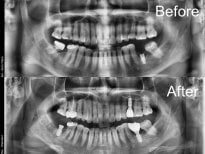

Korean dental clinics routinely use 3D CBCT scans, digital impressions, and computer-guided implant placement. These tools make treatment safer, faster, and more accurate.

After an initial consultation and 3D scan, the dentist plants an implant into the jawbone. If needed, specialists perform bone grafting or sinus lifting at this stage.

- Check reviews and patient photos. Look for real before-and-after cases and feedback from international patients.